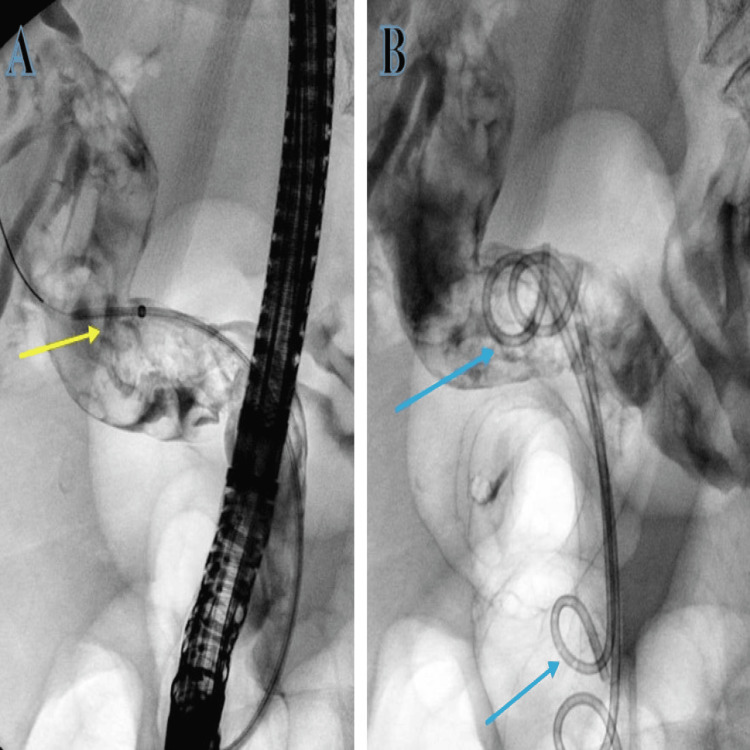

The patient was started on broad-spectrum intravenous antibiotic coverage with piperacillin with tazobactam (Tazocin) for cholangitis and underwent an in-patient ERCP where CBD was noticed to be filled with blood clots during biliary cannulation, but no stones were seen. The clots were successfully evacuated with irrigation followed by the placement of two pigtail stents (Figure 2).